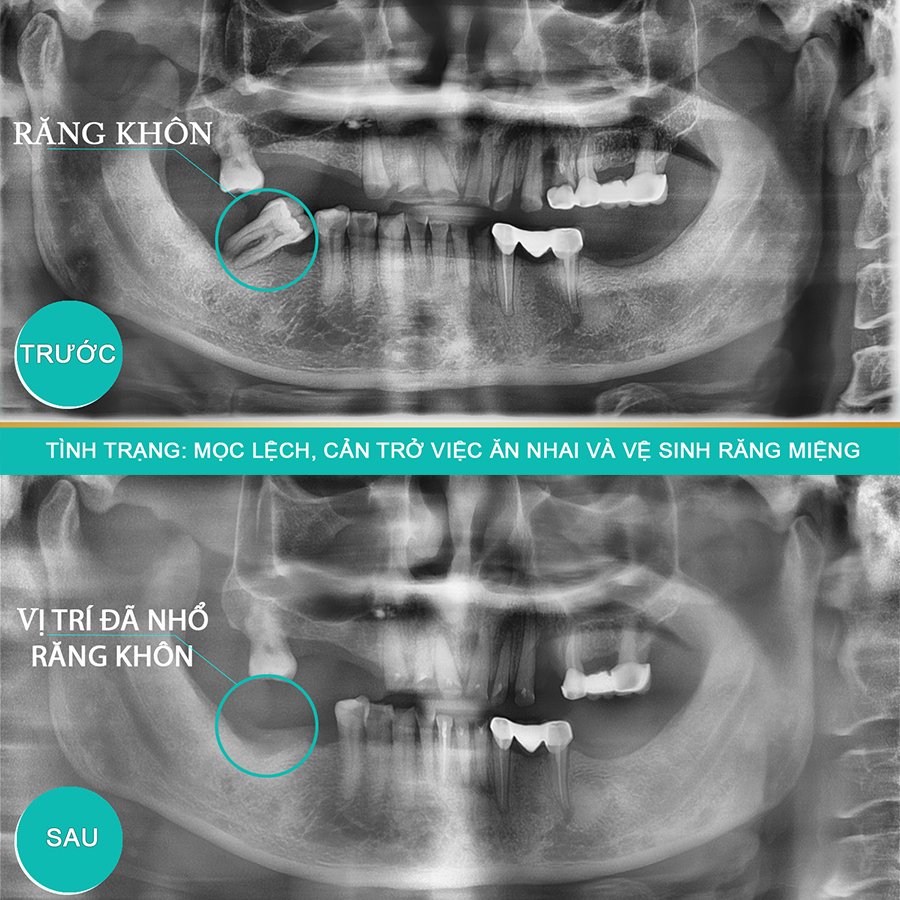

- Chụp phim X-Quang quanh chóp Kỹ thuật số: Nhằm mục đích lựa chọn phương pháp tiểu phẫu thích hợp nhất, qua phim chụp sẽ xác định được hình dáng và số lượng chân răng, hướng răng và góc độ lệch, độ sâu của răng số 7 đã đến tủy hay chưa.